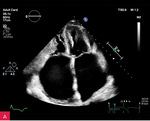

Rycina 1A, B. Zwapnienie w pierścieniu mitralnym (MAC) u podstawy tylnego płatka mitralnego w projekcji przymostkowej w osi długiej LAX (A) i w osi krótkiej SAX (B)

Zwapnienie pierścienia zastawki mitralnej (MAC – mitral annular calcification) stanowi następstwo przewlekłych zmian degeneracyjnych i jest dość często spotykane u osób w starszym wieku (ryc. 1). Serowate zwapnienie pierścienia mitralnego (CCMA – caseous calcification of the mitral annulus) to rzadki, często niedostatecznie rozpoznawany wariant MAC. CCMA stanowi ok. 0,6% wszystkich przypadków MAC, występuje rzadziej niż w 0,1% populacji ogólnej. Częściej dotyka starszych kobiet, szczególnie z nadciśnieniem tętniczym, przewlekłą chorobą nerek lub zaburzeniami gospodarki wapniowo-fosforanowej1,2. Zmiana zazwyczaj obejmuje tylny pierścień zastawki mitralnej i składa się z uwapnionej otoczki oraz wnętrza wypełnionego mieszaniną wapnia, kwasów tłuszczowych i cholesterolu, przypominającą konsystencją pastę do zębów3,4. CCMA może osiągać duże rozmiary, szerząc się w kierunku tylnego płatka mitralnego oraz mięśnia lewej komory w zakresie ściany dolno-bocznej i dolnej.